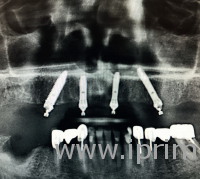

Но обо всем по порядку. Прежде несколько слов о самой технологии. Пятнадцать лет назад Паоло Мало рассчитал, что для того, чтобы протез челюсти выдерживал все нагрузки, достаточно всего четырех, а в отдельных случаях – шести опор. Но установлены они должны быть особым образом. Первые два во фронтальной части челюсти, привычным способом, перпендикулярно линии прикуса. Однако в боковом отделе слева и справа они устанавливаются под углом 30–45 градусов. Это позволяет равномерно распределить нагрузку на все имплантаты.